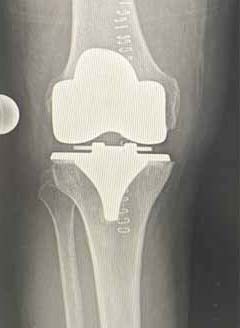

Künstlicher Gelenkersatz

Indikationen:

Ergebnisse:

- Knieprothesen gehören zu den erfolgreichsten Operationen in der Orthopädie.

- Haltbarkeit Knieprothesen: Nach 20 Jahren funktionieren noch rund 90 Prozent aller eingesetzten Knieprothesen zuverlässig.

Unikonyläre Schlittenprothese

Oberfächen Prothese